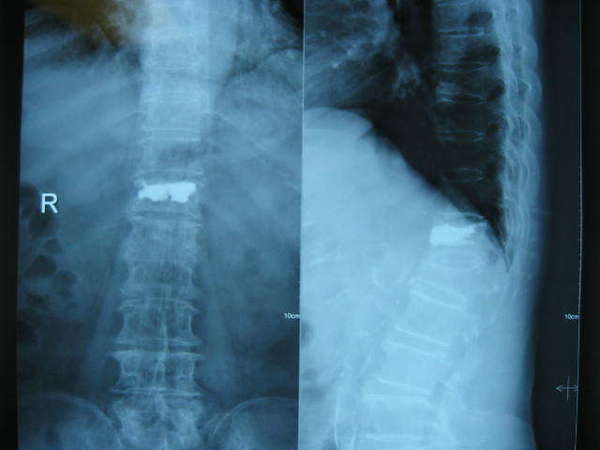

手术前X片---L1及T12均有压缩,且脊柱明显后凸畸形。

比较手术前后显示T12骨折椎体高度恢复,脊柱后凸畸形获得明显改善,填充骨水泥到位并均匀,无渗漏现象.